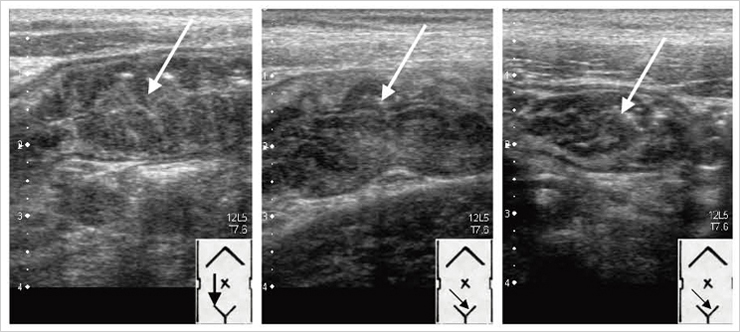

エコー診断のポイントは,臨床症状と検査所見から急性虫垂炎を疑い,積極的にエコーを実施することである。腸腰筋と腸骨動静脈を指標にして,その周囲(外側,腹側,内側)をじっくりと検索し,腫大虫垂(圧迫してもつぶれない直径6mm以上の管腔臓器)を探すのである(図7)。内部に虫垂石を描出できればなおよい。5〜6MHz(年長児や成人では3.5MHzの場合もある)のプローブで全体像を見て,7.5〜8MHz で詳細を確認するとよい。その際,虫垂の向きはさまざまであること,つまり,同じようにプローブを当てても得られる所見は症例によって大きく違うことを銘記しておく必要がある。虫垂炎が疑われるが,腫大虫垂が描出できない場合は膿瘍,糞石,腹水,腸管壁肥厚,腸管への液貯留,腸間膜リンパ節腫大の有無をチェックする。エコーではっきりした所見は得られないが,虫垂炎が疑われる場合は腹部造影CTを行うことを躊躇しない。

図7 急性虫垂炎の2例